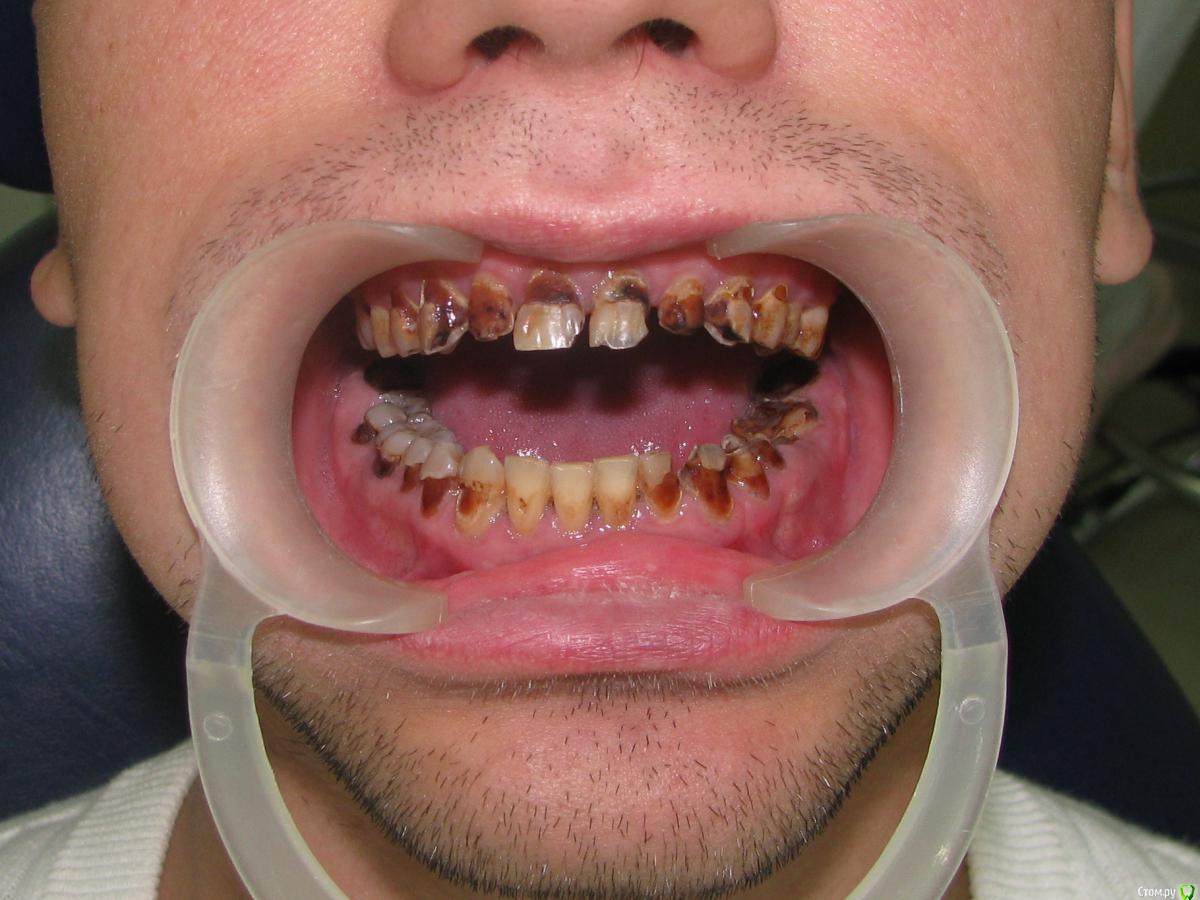

Alex52 Опубликовано 27 июля, 2015 Поделиться Опубликовано 27 июля, 2015 Первичка, наркоту отрицает, со слов практически здоровЛет 20 за компом - с этим и связывает свое состояние. Так и хочется поставить такой диагноз - компьютерный некроз, но не понимаю патогенез, он же не с куском плутония целовался.Пигментированные ткани почти все мягкие (не сильно), на температуру реагируют.Коллега предлагает сделать курс ремотерапии, чтобы пигментация была с крепитацией, а потом лечить по диагнозу, может что и живое останется и вкладок поменьше - но что-то слабо верится в такой курс. Ссылка на комментарий

molchanoff Опубликовано 27 июля, 2015 Поделиться Опубликовано 27 июля, 2015 ага 20 лет просидел за компом не чистя зубы вот и результат Ссылка на комментарий

Doc.IQ Опубликовано 27 июля, 2015 Поделиться Опубликовано 27 июля, 2015 100% чем то балуется..Ремотерапия в данном случае результатов не даст..произвести удаление 18,17,28,38,48,36,сделать некрэктомию оставшихся зубов,оценить полученный результат,после этого выбирать дизайн препаровки,ортопедическую конструкцию,материал..импланты само собой в дистальных отделах..кажется мне,что без кладок кое где будет не обойтись... Ссылка на комментарий

brg Опубликовано 28 июля, 2015 Поделиться Опубликовано 28 июля, 2015 курит?Курит!!!Смеси-спайсы, был у меня похожил как на фотоОн сам сразу сказал -курил, завязал.Хочу новые зубы 1 Ссылка на комментарий

red_butler Опубликовано 28 июля, 2015 Поделиться Опубликовано 28 июля, 2015 голосую за амфетамин 3 Ссылка на комментарий